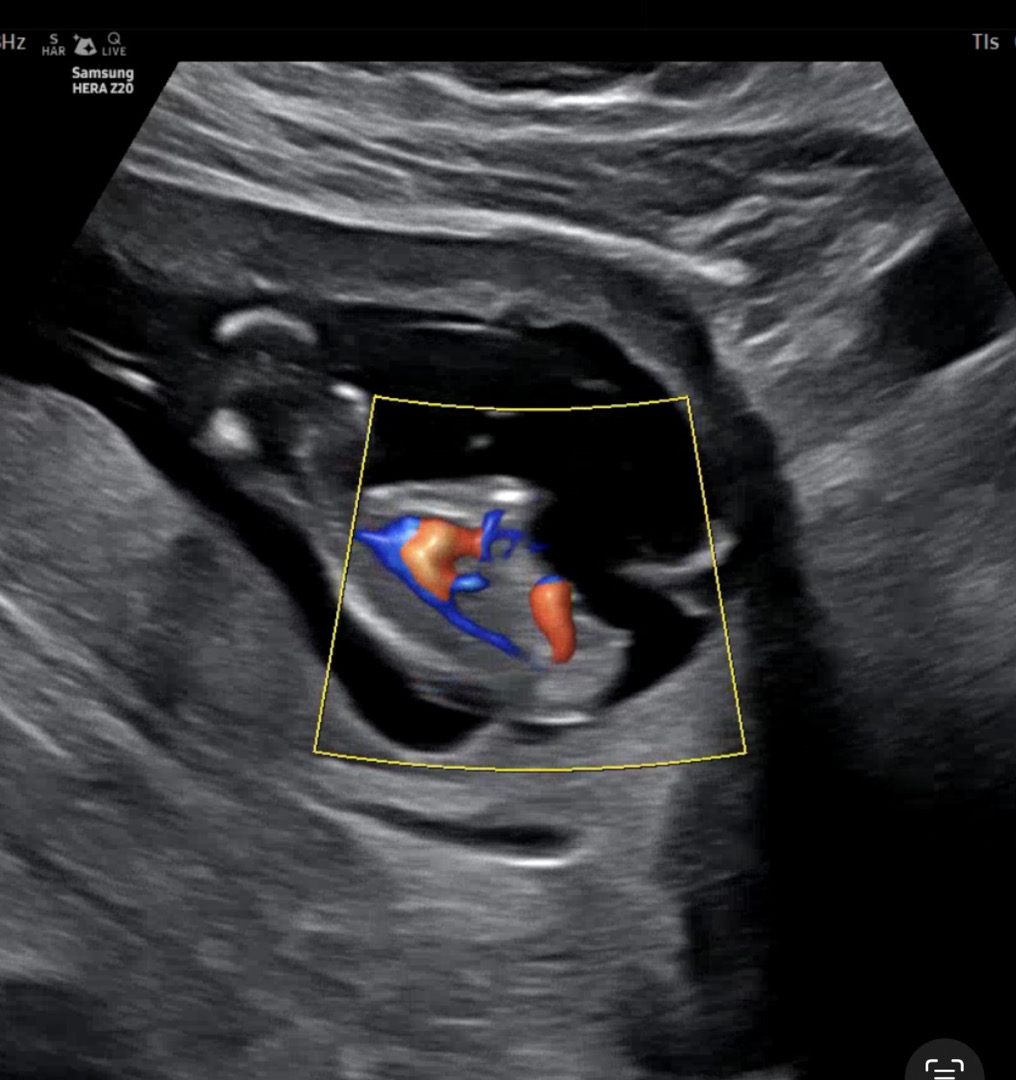

12주1일 각도법

춈파 영상 캡쳐하긴했는데 각도법 봐지는 사진 맞을까용 맞으면 아들인지 딸인지~~!! 많이 봐주세용ㅋㅋㅋ

딸같아요